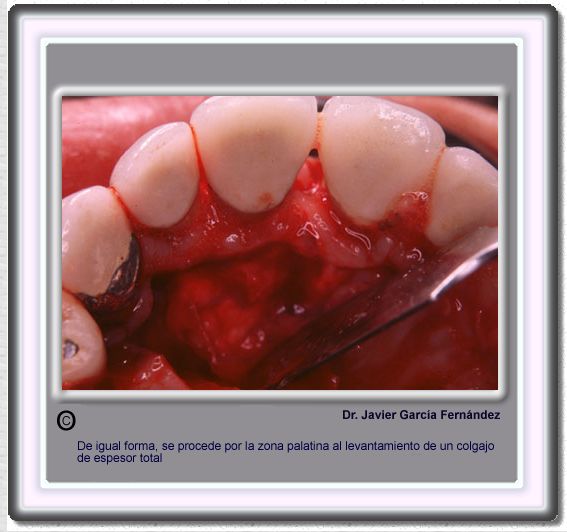

image 760